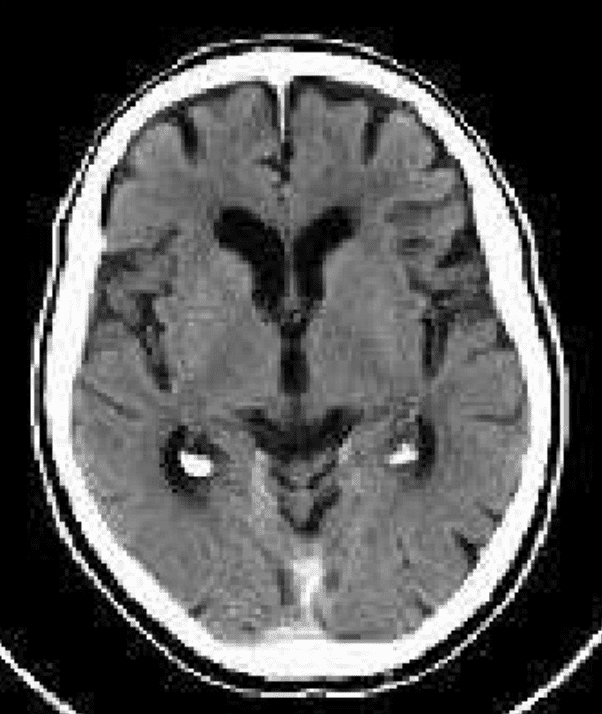

The next day was in another hospital: an MRI scan of the entire body and brain, a cardiology test, breast research and some other stuff. I was a bit nervous about the MRI. I am very sensitive to electro magnetic fields. How would I feel about going into this electro magnetic tunnel, not being able to move for 45 mins? And what about the contrast liquid they would put into my body? I felt slightly nauseous, just thinking about it. Fortunately the doctor recommended doing the MRI without contrast liquid, since it was preventative and we were not looking for something specific. A few minutes later I found myself being prepared to go into the MRI ‘tunnel’. It is interesting that if you do this as part of a prescan, you feel completely different than when you are sick. No nervousness about what they are going to find, no discomfort, no stress, just a mild curiosity. The sound the MRI makes is very loud. Like standing in front of the speakers of a techno festival… Strange enough, it kind of relaxed me. I had no problems at all being completely immobile for 45 mins. Weird, because when I try to meditate, I can’t sit still for 5 minutes! Afterwards the radiologist explains the 1500(!) MRI pictures taken of my body and brain. Except for some small damage from the whiplash, visible in my brain, there is nothing remarkable. Alzheimer’s not measurable on MRI, unfortunately. Oh, by the way, he mentions that my brain has asymmetric brain ventricles (fluid chambers). Normal ventricles look something like the first picture and mine look more like the second one (but then reversed: my ventricles are on the left side of my brain):

He explains this has been the way like this since I was born and it’s nothing to worry about. He also says it is not quite common. Anybody has any information on this?